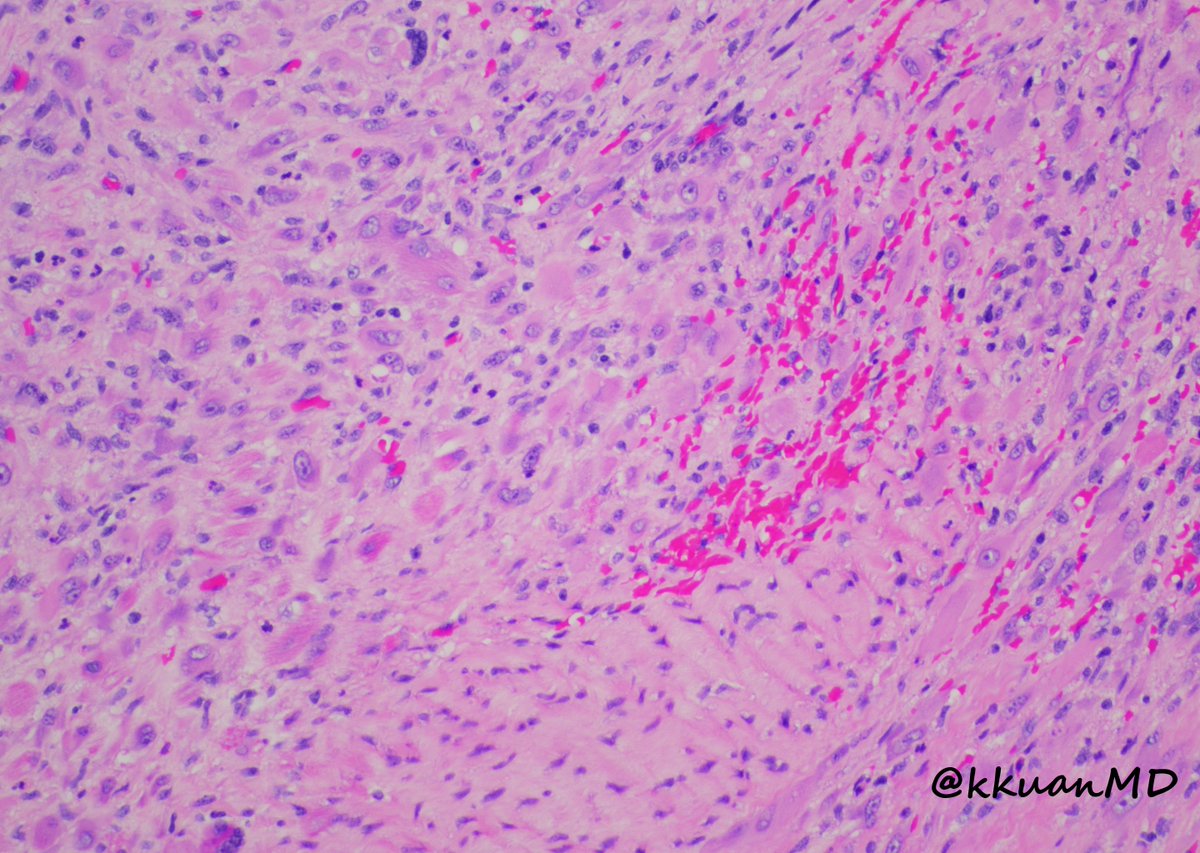

63/male with abdominal lymphadenopathy. DQ gave the initial clue to hemepath diagnosis. Positive CD3/5/7/25. CD30 diffuse, ALK1/CD20 negative. CD30+ Mature T-cell lymphoma. D/D ALCL or ATLL HTLV1 is positive! #cyto #hemepath #PathTwitter Kevin Kuan Yanhua Wang #bridgingcytoheme

Metastatic GIST to an abdominal lymph node- With both epithelioid and spindle cell features. Positive for DOG1, CD34 and CD117(shown here). #pathtwitter #cytology #surgpath #path Kevin Kuan